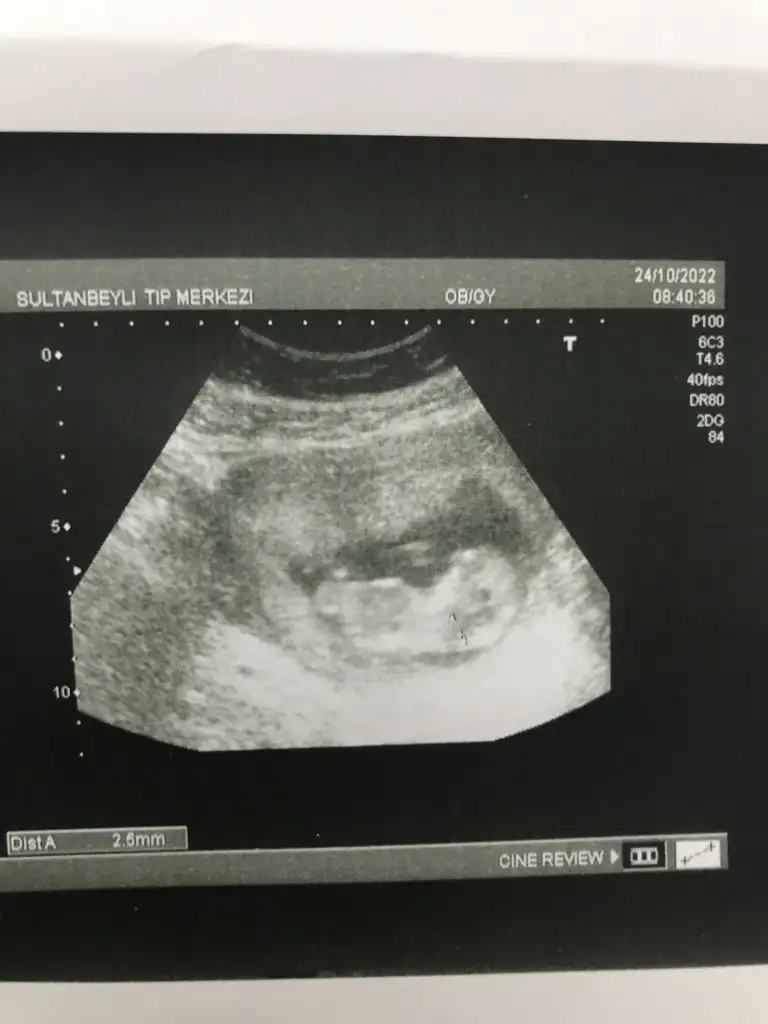

5 ve 14. haftaya kadar olan ultrason fotolarınızı paylaşın. Vajinadan mı yoksa karından mı çekildiğini ve kaç haftalık olduğunu da mutlaka belirtin.

Erkeğe benziyor canım11haftalik

Karındansa kızMerhaba kızlar banada tahmin yapabilcek var mı? Karından 7+4 haftalık

Canım erkeğe benziyor11haftalik